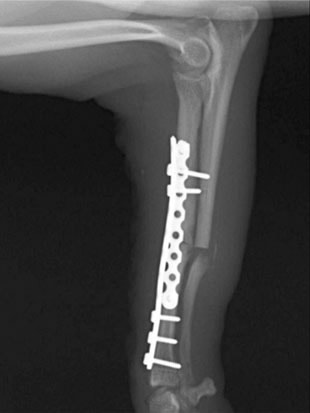

トイプードル 右遠位橈尺骨短斜骨折のALPSによる内固定

LCPは、スクリュー(ネジ)とプレート(金属の板)をロックする特殊な構造により骨折部位を固定する新しい世代のプレートシステムです。ひとつのホールでロッキングスクリューとスタンダードスクリューの使用を選択できるユニークな構造をしているため、骨折断端間の圧迫を目的とした従来型プレート固定法に加え、高い角度安定性を有するロッキングスクリューを用いた固定法の選択が可能です。従来のプレートシステムでは困難だった部分の骨折や癒合不全の症例に高い治療効果をもたらします。

当院ではAdvanced Locking plate system(ALPS)と、Locking compression plate system(LCPS)という骨接合法で骨折症例の治療を行っています。